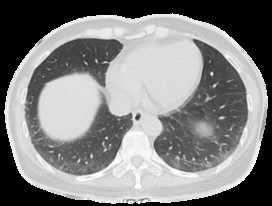

Figure 3: Peripheral reticular interstitial lesions of the lower lobes of lungs.

Our female patient presented with progressive proximal lower limb muscle weakness over 3 years, impaired activities of daily living, elevated muscle enzymes, and thigh muscle atrophy developing within only 7 months after disease onset. Throughout the disease, the patient did not experience fever or signs of infection. Regarding her medical history, she had not used any medications affecting muscle function over the past 3 years, did not consume alcohol, and had no exposure to toxins. Paraclinical investigations, including lumbar MRI, excluded spinal cord and lumbar root pathology. Electromyography of the lower limbs showed no peripheral neuropathy. Electrolyte levels, thyroid function tests, and blood glucose were all within normal limits. Autoimmune tests revealed a high positivity for anti-SRP antibodies. Therefore, the clinical and paraclinical features of our case are consistent with those reported in the literature [1,2]. Anti-SRP myopathy is more common in women than in men (with a 3:1 ratio) and typically affects middle-aged individuals. These patients usually present with rapid, symmetrical proximal muscle weakness, severe muscle pain, significantly elevated muscle enzymes, and ultimately muscle atrophy and disability if not treated promptly. Furthermore, these patients tend to recover poorly, with only half achieving near-normal or full muscle strength after 4 years of immunosuppressive therapy. Approximately 19% of patients with Anti-SRP myopathy develop pulmonary involvement on chest CT, primarily exhibiting a non-specific interstitial pneumonia (NSIP) pattern [6,7]. While most of these cases present with mild to moderate symptoms and slow disease progression, this patient cohort frequently experiences a higher incidence of interstitial lung disease and respiratory failure compared to those with Anti-HMG-CR myopathy [6]. This is particularly true when diagnosis and initiation of immunosuppressive therapy are delayed. For our patient, the extended duration of the diagnostic workup and the subsequent delay in treatment initiation directly contributed to the rapid development of exertional dyspnea and significant lung lesions on chest CT within merely four months of a definitive diagnosis. Therefore, Anti-SRP myopathy remains one of the most debilitating autoimmune myopathies, which underscores the importance of early diagnosis and intervention.